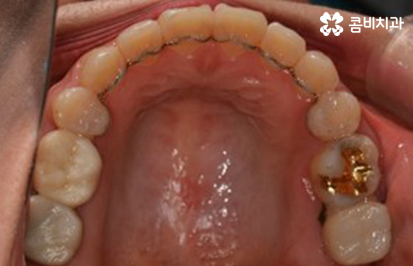

교정이 시작되기 전에 충치가 있다면 미리 치료 후 진행합니다.

(좌) 얼굴을 고려하여 돌출입을 개선하는 치료 계획을 세움, (우) 사랑니 발치와 상악 14,24 / 하악 34,44 치아 발치 진행

교정이 시작된 후 경과 - 발치를 했던 부위의 치아 사이 빈 공간이 사라짐

장치를 풀어내고 유지 관리가 시작된 모습

유지 장치가 부착되어 있는 모습